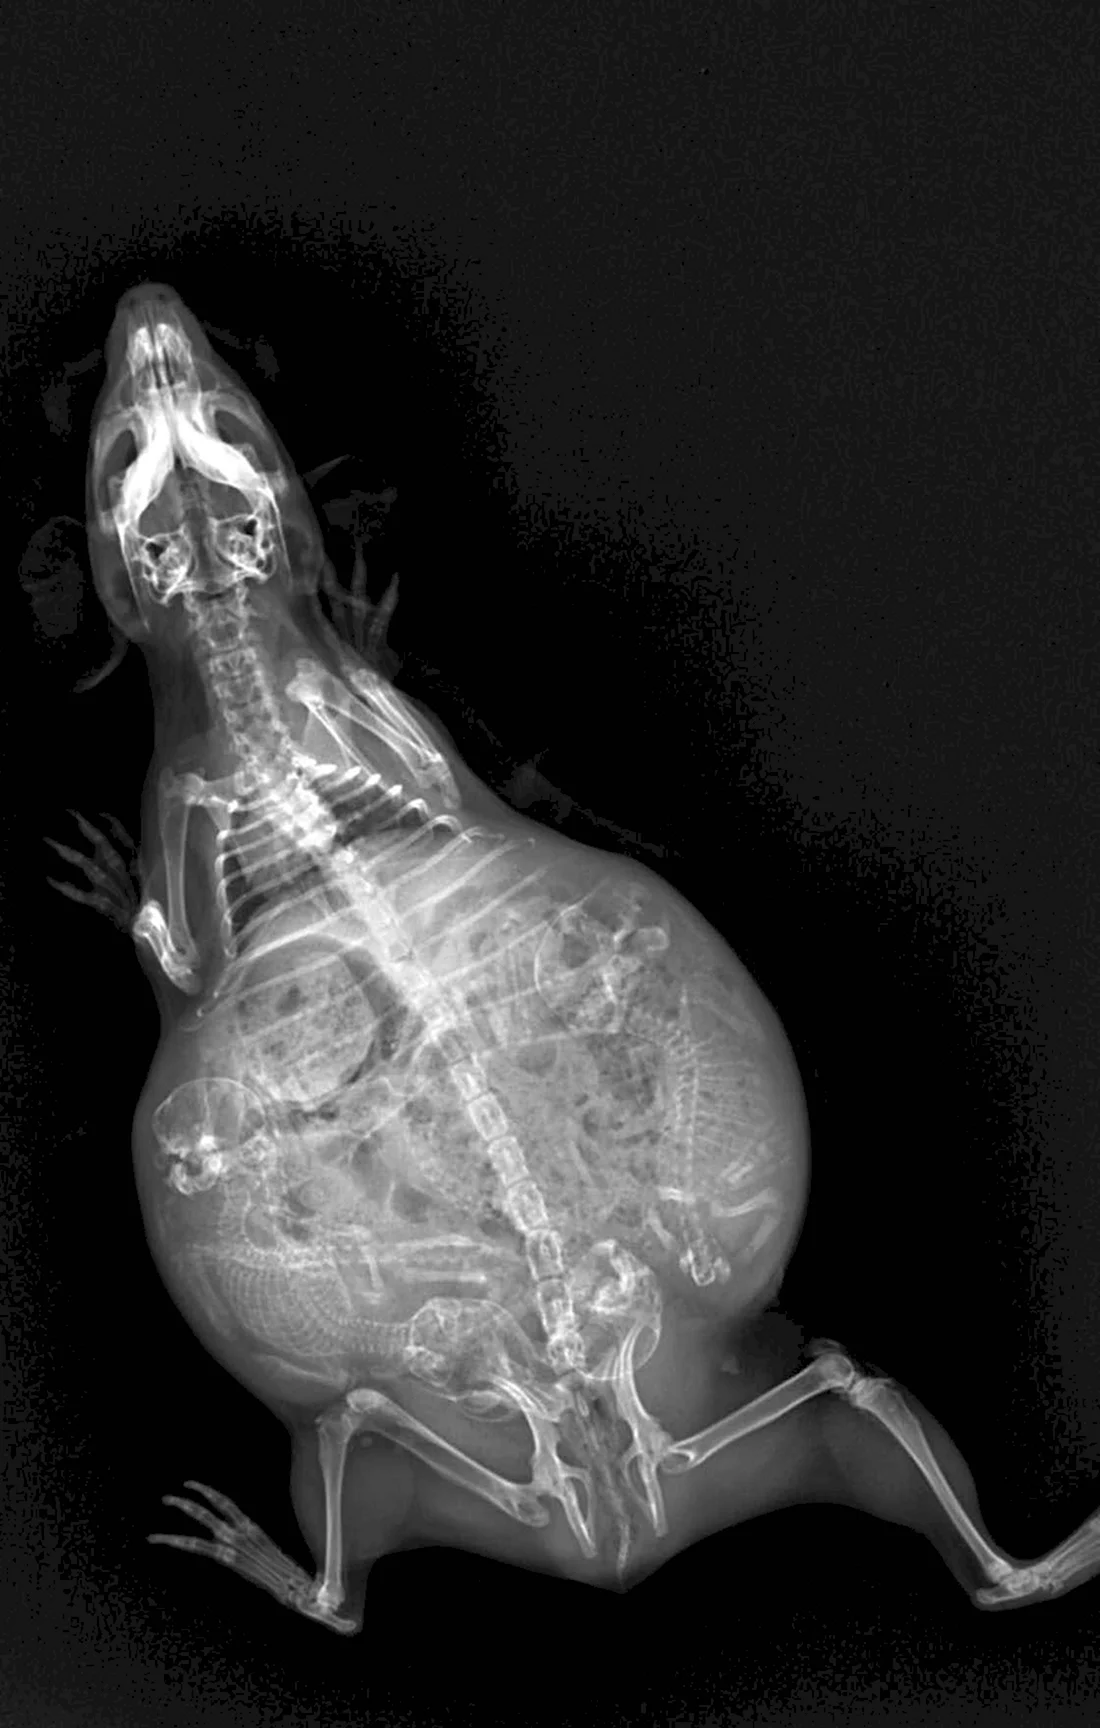

Погрузитесь в волшебный мир развития эмбриона кошки с помощью этой захватывающей галереи фотографий! Вас ждут 39 потрясающих фото и картинок, которые позволят вам увидеть каждый этап развития эмбриона. Эта подборка фотографий сразу привлечет ваше внимание и заставит задуматься о том, насколько удивительным может быть природа. Порадуйте свои глаза этой удивительной коллекцией фотографий и узнайте больше об удивительной жизни эмбрионов кошек!